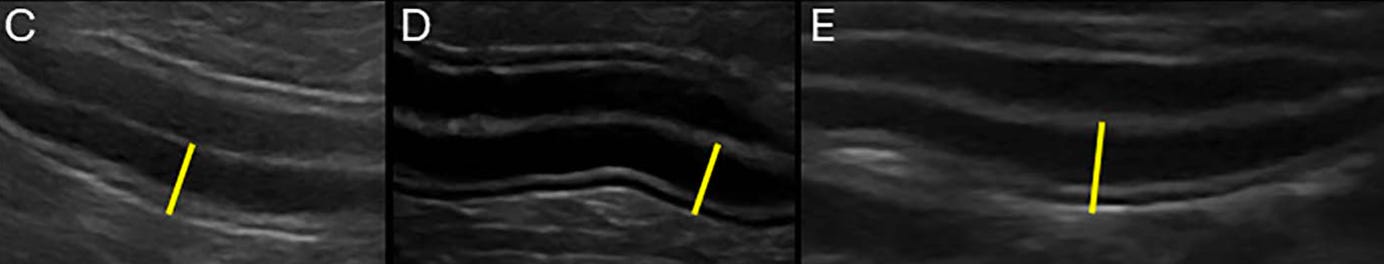

Diferentes grados de engrosamiento de la pared intestinal y la mucosa: